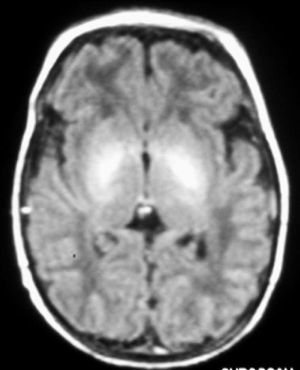

Fig. 3. Resonancia magnética.Secuencia T2 turbo en plano axial. Tenue hiperseñal al nivel de núcleos palidales de forma bilateral.

A las 48 horas de su ingreso presenta una crisis de hipertonía, motivo por el que se realiza una resonancia magnética.